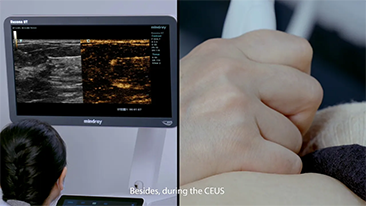

L'imagerie de contraste joue un r?le important en cas de lĂŠsions hĂŠpatiques focales, par exemple hĂŠmangiome ou cancer hĂŠpatique. La technologie d'imagerie de contraste UWN+ ultra-large et non linĂŠaire offre une meilleure pĂŠnĂŠtration, un rapport contraste-tissu plus ĂŠlevĂŠ, avec un index mĂŠcanique (IM) plus faible et une observation plus longue du temps de perfusion.